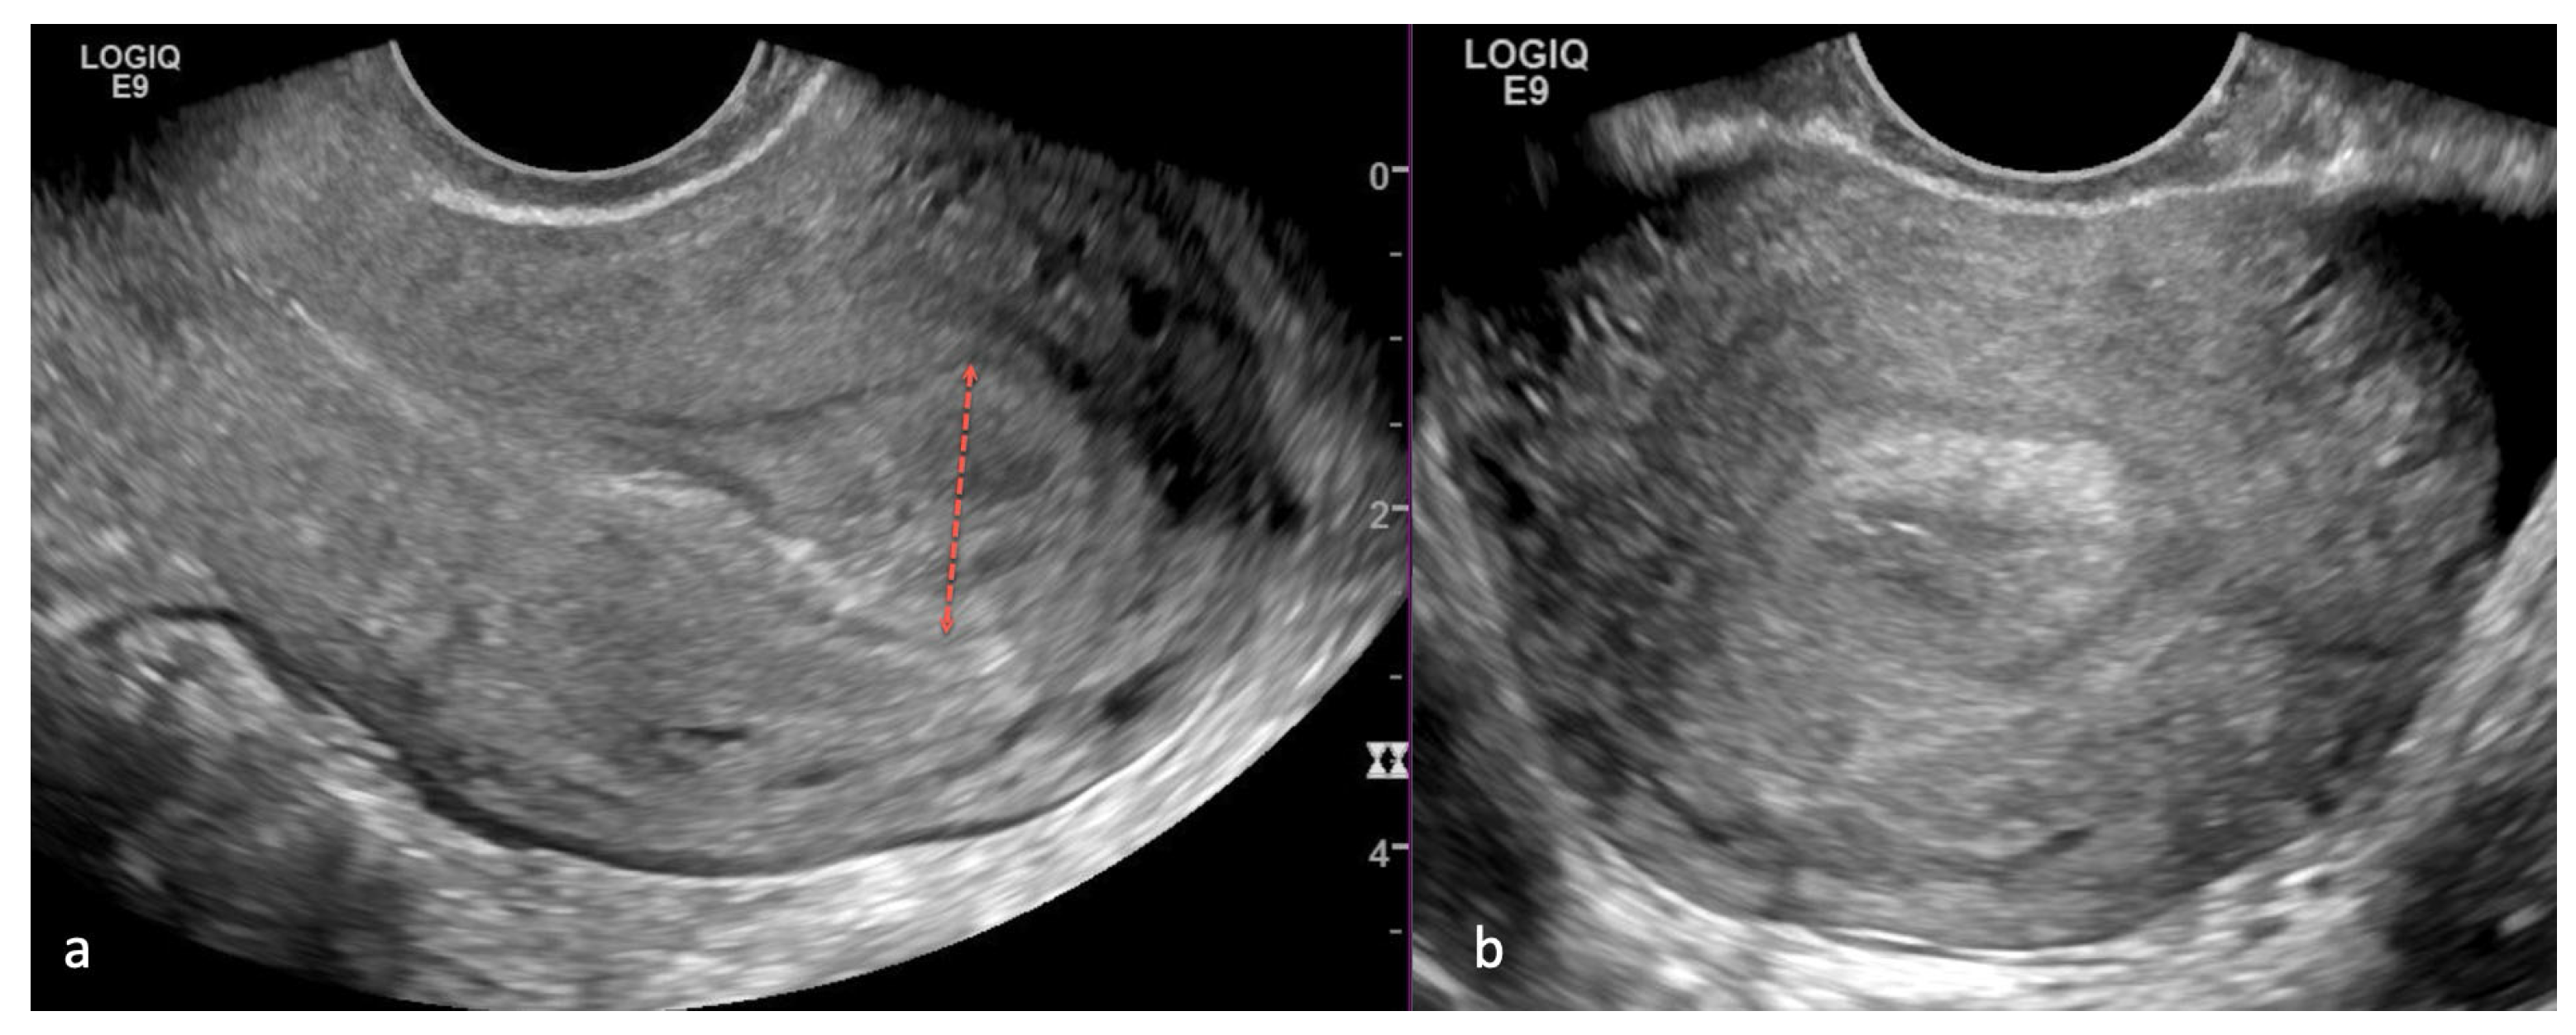

5.1. Ultrasound (US)

- Gentry-Maharaj, A.; Karpinskyj, C. Current and future approaches to screening for endometrial cancer. Best Pract. Res. Clin. Obstet. Gynaecol. 2020, 65, 79–97. [Google Scholar] [CrossRef]

- Robbins, J.B.; Sadowski, E.A.; Maturen, K.E.; Akin, E.A.; Ascher, S.M.; Brook, O.R.; Cassella, C.R.; Dassel, M.; Henrichsen, T.L.; Learman, L.A.; et al. ACR Appropriateness Criteria® Abnormal Uterine Bleeding. J. Am. Coll. Radiol. 2020, 17, S336–S345. [Google Scholar] [CrossRef]

- ACOG Publications. ACOG Committee Opinion No. 734: The Role of Transvaginal Ultrasonography in Evaluating the Endometrium of Women With Postmenopausal Bleeding. Obstet. Gynecol. 2018, 131, 945–946. [Google Scholar] [CrossRef]

- Wong, A.S.; Lao, T.T.; Cheung, C.W.; Yeung, S.W.; Fan, H.L.; Ng, P.S.; Yuen, P.M.; Sahota, D.S. Reappraisal of endometrial thickness for the detection of endometrial cancer in postmenopausal bleeding: A retrospective cohort study. BJOG Int. J. Obstet. Gynaecol. 2016, 123, 439–446. [Google Scholar] [CrossRef] [PubMed]

- Gull, B.; Karlsson, B.; Milsom, I.; Granberg, S. Can ultrasound replace dilation and curettage? A longitudinal evaluation of postmenopausal bleeding and transvaginal sonographic measurement of the endometrium as predictors of endometrial cancer. Am. J. Obstet. Gynecol. 2003, 188, 401–408. [Google Scholar] [CrossRef] [PubMed]

- Karlsson, B.; Granberg, S.; Wikland, M.; Ylöstalo, P.; Torvid, K.; Marsal, K.; Valentin, L. Transvaginal ultrasonography of the endometrium in women with postmenopausal bleeding—A Nordic multicenter study. Am. J. Obstet. Gynecol. 1995, 172, 1488–1494. [Google Scholar] [CrossRef] [PubMed]

- Ferrazzi, E.; Torri, V.; Trio, D.; Zannoni, E.; Filiberto, S.; Dordoni, D. Sonographic endometrial thickness: A useful test to predict atrophy in patients with postmenopausal bleeding. An Italian multicenter study. Ultrasound Obstet. Gynecol. 1996, 7, 315–321. [Google Scholar] [CrossRef] [PubMed]

- Ziogas, A.; Xydias, E.; Kalantzi, S.; Papageorgouli, D.; Liasidi, P.N.; Lamari, I.; Daponte, A. The diagnostic accuracy of 3D ultrasound compared to 2D ultrasound and MRI in the assessment of deep myometrial invasion in endometrial cancer patients: A systematic review. Taiwan. J. Obstet. Gynecol. 2022, 61, 746–754. [Google Scholar] [CrossRef] [PubMed]

- Spagnol, G.; Noventa, M.; Bonaldo, G.; Marchetti, M.; Vitagliano, A.; Laganà, A.S.; Cavallin, F.; Scioscia, M.; Saccardi, C.; Tozzi, R. Three-dimensional transvaginal ultrasound vs magnetic resonance imaging for preoperative staging of deep myometrial and cervical invasion in patients with endometrial cancer: Systematic review and meta-analysis. Ultrasound Obstet. Gynecol. 2022, 60, 604–611. [Google Scholar] [CrossRef] [PubMed]

- Green, R.W.; Epstein, E. Dynamic contrast-enhanced ultrasound improves diagnostic performance in endometrial cancer staging. Ultrasound Obstet. Gynecol. 2020, 56, 96–105. [Google Scholar] [CrossRef] [PubMed]